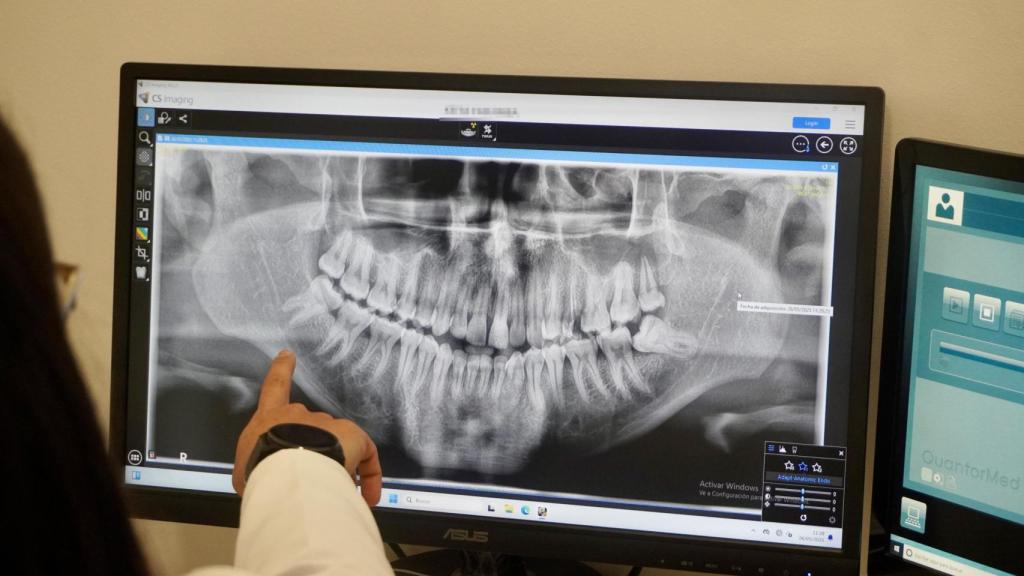

Luego viene la parte técnica. Se le hace una radiografía de la mano izquierda. La imagen se compara con un atlas de maduración ósea elaborado en Estados Unidos en los años 50. Si la mano revela que tiene menos de 17 años, se cierra el informe. Si da indicios de 18 o 19, se pasa al siguiente escalón: una tomografía dental. La maduración de los terceros molares —las muelas del juicio— permite estimar un rango probable de edad.

La Dra. Domínguez visualiza una ortopantomografía recién realizada de uno de los migrantes.

La Dra. Domínguez visualiza una ortopantomografía recién realizada de uno de los migrantes. Julio César R. A.